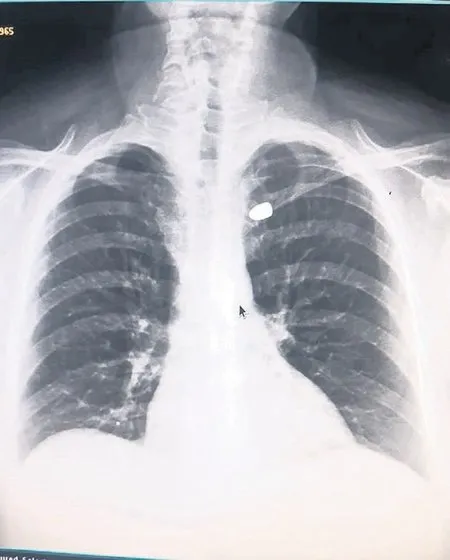

Olcay Hellaç, ilk müdahaleyi yaptığı eşini sırtında eve taşıdı. Durumu hemen sağlık ekiplerine bildiren Hellaç ailesi, kısa sürede olay yerine gelen ambulansla Karadeniz Teknik Üniversitesi Farabi Hastanesi’ne ulaştı. Yapılan tetkiklerde Hellaç’ın göğsüne bir yorgun merminin isabet ettiği belirlendi.

Mermi Kemikten Durdu: “2 Santimetre Aşağıda Ölüm Olabilirdi”

Göğüs Cerrahisi Uzmanı Prof. Dr. Celal Tekinbaş, hastanın sağlık durumuyla ilgili şu açıklamayı yaptı:

❝Hastamızın köprücük kemiği kırılmış durumda. Mermi kemiği delerek durdu ve şu an göğüs boşluğunda. Şeker hastası olması nedeniyle ameliyatı erteledik. 3 aylık kan şekeri seviyesi normale indiğinde cerrahi müdahaleyle mermiyi çıkaracağız. Ancak belirtmek gerekir ki, mermi yalnızca 2 santimetre aşağıya isabet etseydi, büyük damarlara zarar verebilir ve hayati tehlike doğurabilirdi.❞